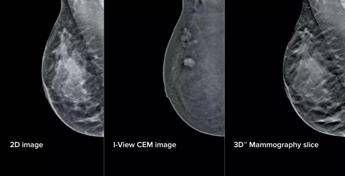

Grazie all'integrazione di intelligenza artificiale e mammografi di ultima generazione, la Uosd Diagnostica per immagini in senologia ha messo a punto "un intervento tecnologico profondo che coinvolge strumenti, software e flussi di lavoro, ottimizzando l'attività dei professionisti e rendendo i percorsi diagnostici più semplici e meno gravosi" per le pazienti, spiega l'Ao in una nota. La Breast Unit dell'ospedale romano, si legge, "risulta ad oggi l'unica struttura pubblica in Italia a vantare una configurazione così completa e all'avanguardia per quanto riguarda i mammografi del segmento". L'aggiornamento – illustra il San Camillo – si compone di elementi fisici e virtuali in due ambiti principali: la mammografia con refertazione e la biopsia mammaria. Sul fronte della refertazione, è stata introdotta una nuova workstation con monitor ad altissima risoluzione e strumenti avanzati di analisi delle immagini. Un software dedicato consente di valutare in modo oggettivo la densità del tessuto mammario, un elemento importante perché associato al rischio di tumore al seno. A questo si aggiunge un software che analizza struttura e densità del tessuto mammario, tecnologia di tomosintesi avanzata che riduce del 66% il numero di slice – le 'fettine' spesse 1 mm di tessuto mammario acquisite dal mammografo – mantenendo le stesse informazioni diagnostiche. Meno immagini da scorrere significa meno affaticamento: una riduzione del carico cognitivo per il radiologo stimata intorno al 13%, con benefici concreti soprattutto nelle sessioni di lettura multipla. A supporto dei medici – prosegue la nota – è stato integrato anche un sistema di intelligenza artificiale che evidenzia automaticamente le aree sospette sulle singole slice, come microcalcificazioni o alterazioni del tessuto, e fornisce indicazioni utili per la priorità di lettura. Studi preliminari indicano "un miglioramento della capacità di individuare lesioni fino al 9%". Sul fronte della biopsia mammaria, i mammografi di ultima generazione consentono di eseguire la procedura direttamente a partire da immagini con contrasto, unendo in un unico passaggio la localizzazione della lesione e il prelievo bioptico. Per la paziente questo si traduce in un percorso interamente nello stesso reparto, senza la necessità di ricorrere alla risonanza magnetica chiusa. Un apposito dispositivo meccanico permette inoltre di raggiungere anche le lesioni in posizioni difficili. "Come ingegneri clinici, ci impegniamo a garantire che la tecnologia a servizio della medicina sia costantemente appropriata e all'avanguardia – afferma Annarita Caporaso, direttore Uoc Ingegneria clinica – Nel progetto in questione ci siamo posti l'obiettivo di coadiuvare l'occhio e l'esperienza del medico con un'architettura tecnologica capace di potenziarne le capacità analitiche. Attraverso algoritmi di intelligenza artificiale studiati per migliorare la qualità diagnostica a supporto della valutazione clinica, l'innovazione diventa uno strumento concreto al servizio della diagnosi. Non si tratta solo di potenza di calcolo, ma di un'autentica efficienza dei processi: riducendo drasticamente il volume di dati da analizzare, migliorando così il flusso di lavoro. Abbiamo messo a punto un'infrastruttura solida che garantisce la massima sicurezza clinica e trasforma l'innovazione in un percorso diagnostico fluido, preciso e ultramoderno". Aggiunge Francesca Svegliati, responsabile Uosd Diagnostica per immagini in senologia: "Oggi abbiamo strumenti che ci permettono di essere ancora più precisi, individuando dettagli e microcalcificazioni difficili da rilevare a occhio nudo. Questo rafforza la sicurezza diagnostica e ci consente di offrire risposte più rapide. L'upgrade più importante riguarda le biopsie guidate con mezzo di contrasto (Cem): poter sottoporre a biopsia lesioni non altrimenti evidenziabili o visibili solo in risonanza magnetica ci consente di raggiungere una precisione nella stadiazione locale già in reparto senza ricorrere a procedure diagnostiche – biopsia Rm guidata – che risultano molto più impattanti sul percorso della paziente. Per chi si rivolge a noi significa meno attesa e meno tensione, con un percorso più fluido, semplice e accurato".